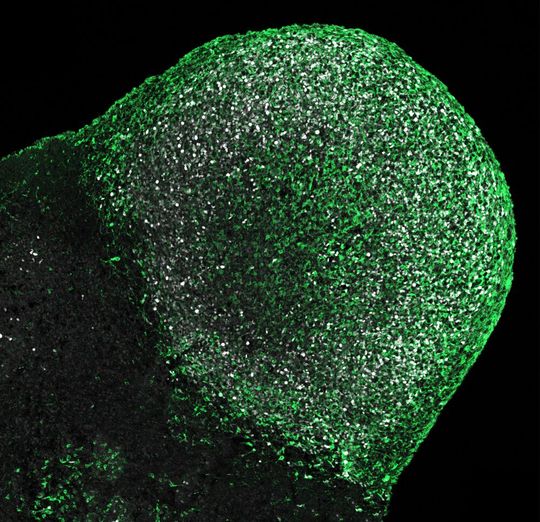

Tumor auf einem von einem Tuberöse-Sklerose (TSC)-Patienten stammenden Hirnorganoid

(Bild: Knoblich/IMBA)

Für die von Corsini und Knoblich geleitete Studie züchtete das Team Hirnorganoide von mehreren betroffenen Patientinnen und Patienten. Diese Methode erlaubt es, molekulare und zelluläre Mechanismen zu untersuchen, die in den Gehirnen der Betroffenen zu einem bestimmten Zeitpunkt der Entwicklung existierten. „Mit diesem Ansatz fanden wir heraus, dass in den Organoiden genau wie in den Gehirnen der Patienten Tumore wuchsen. Die Organoide wiesen auch ungeordnete Bereiche auf, die den Tubern der Patienten ähnelten“, erklärt Oliver Eichmüller, Erstautor der Studie.